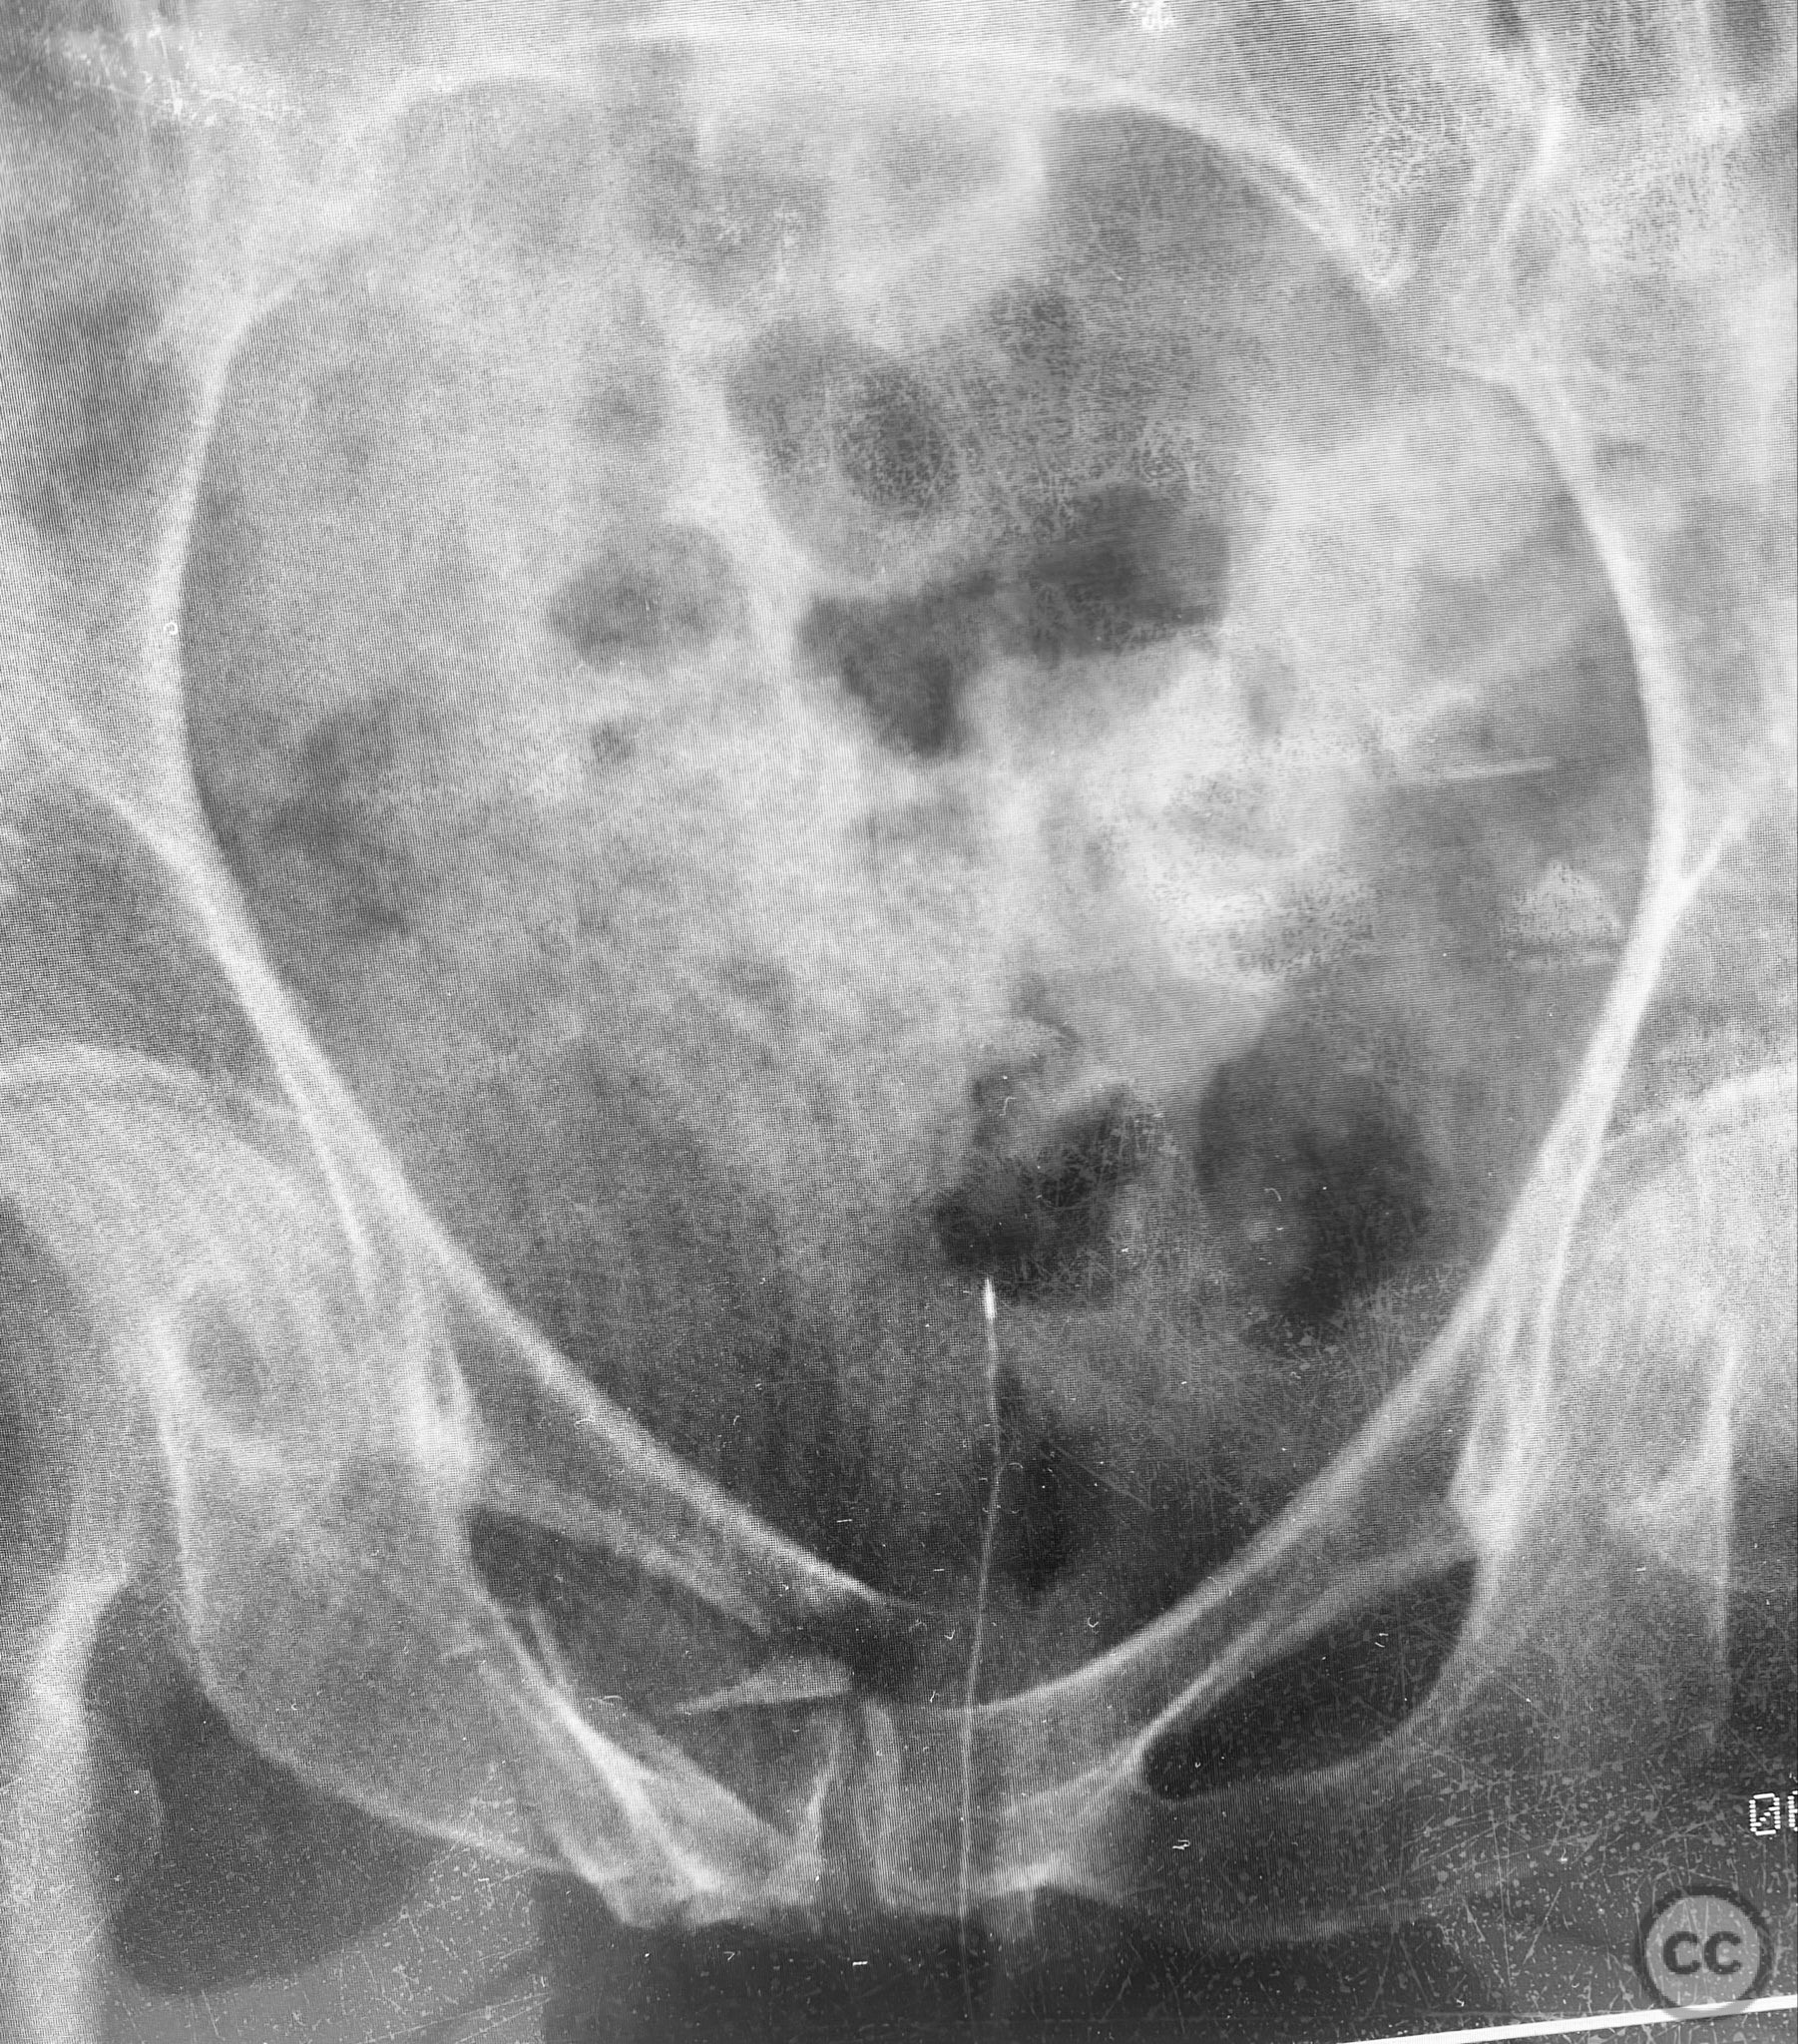

Intraoperatively, EUAF confirmed instability sites and allowed dynamic assessment of reduction. IS screws were placed in the upper sacral path for posterior stabilization. The anterior ring was stabilized with a retrograde 4.5mm blunt tip cortical screw, advanced by turning with a screwdriver, utilizing the variable width of the ramus isthmus for optimal implant fit and stability. The technique permitted percutaneous fixation with minimal soft tissue disruption.

Postoperative protocol:   Postoperatively, the patient was mobilized with walker assistance and reported comfortable ambulation following percutaneous screw fixation.

Orthopaedic implants used:   7.0mm cannulated iliosacral screws; 4.5mm blunt tip cortical threaded screw